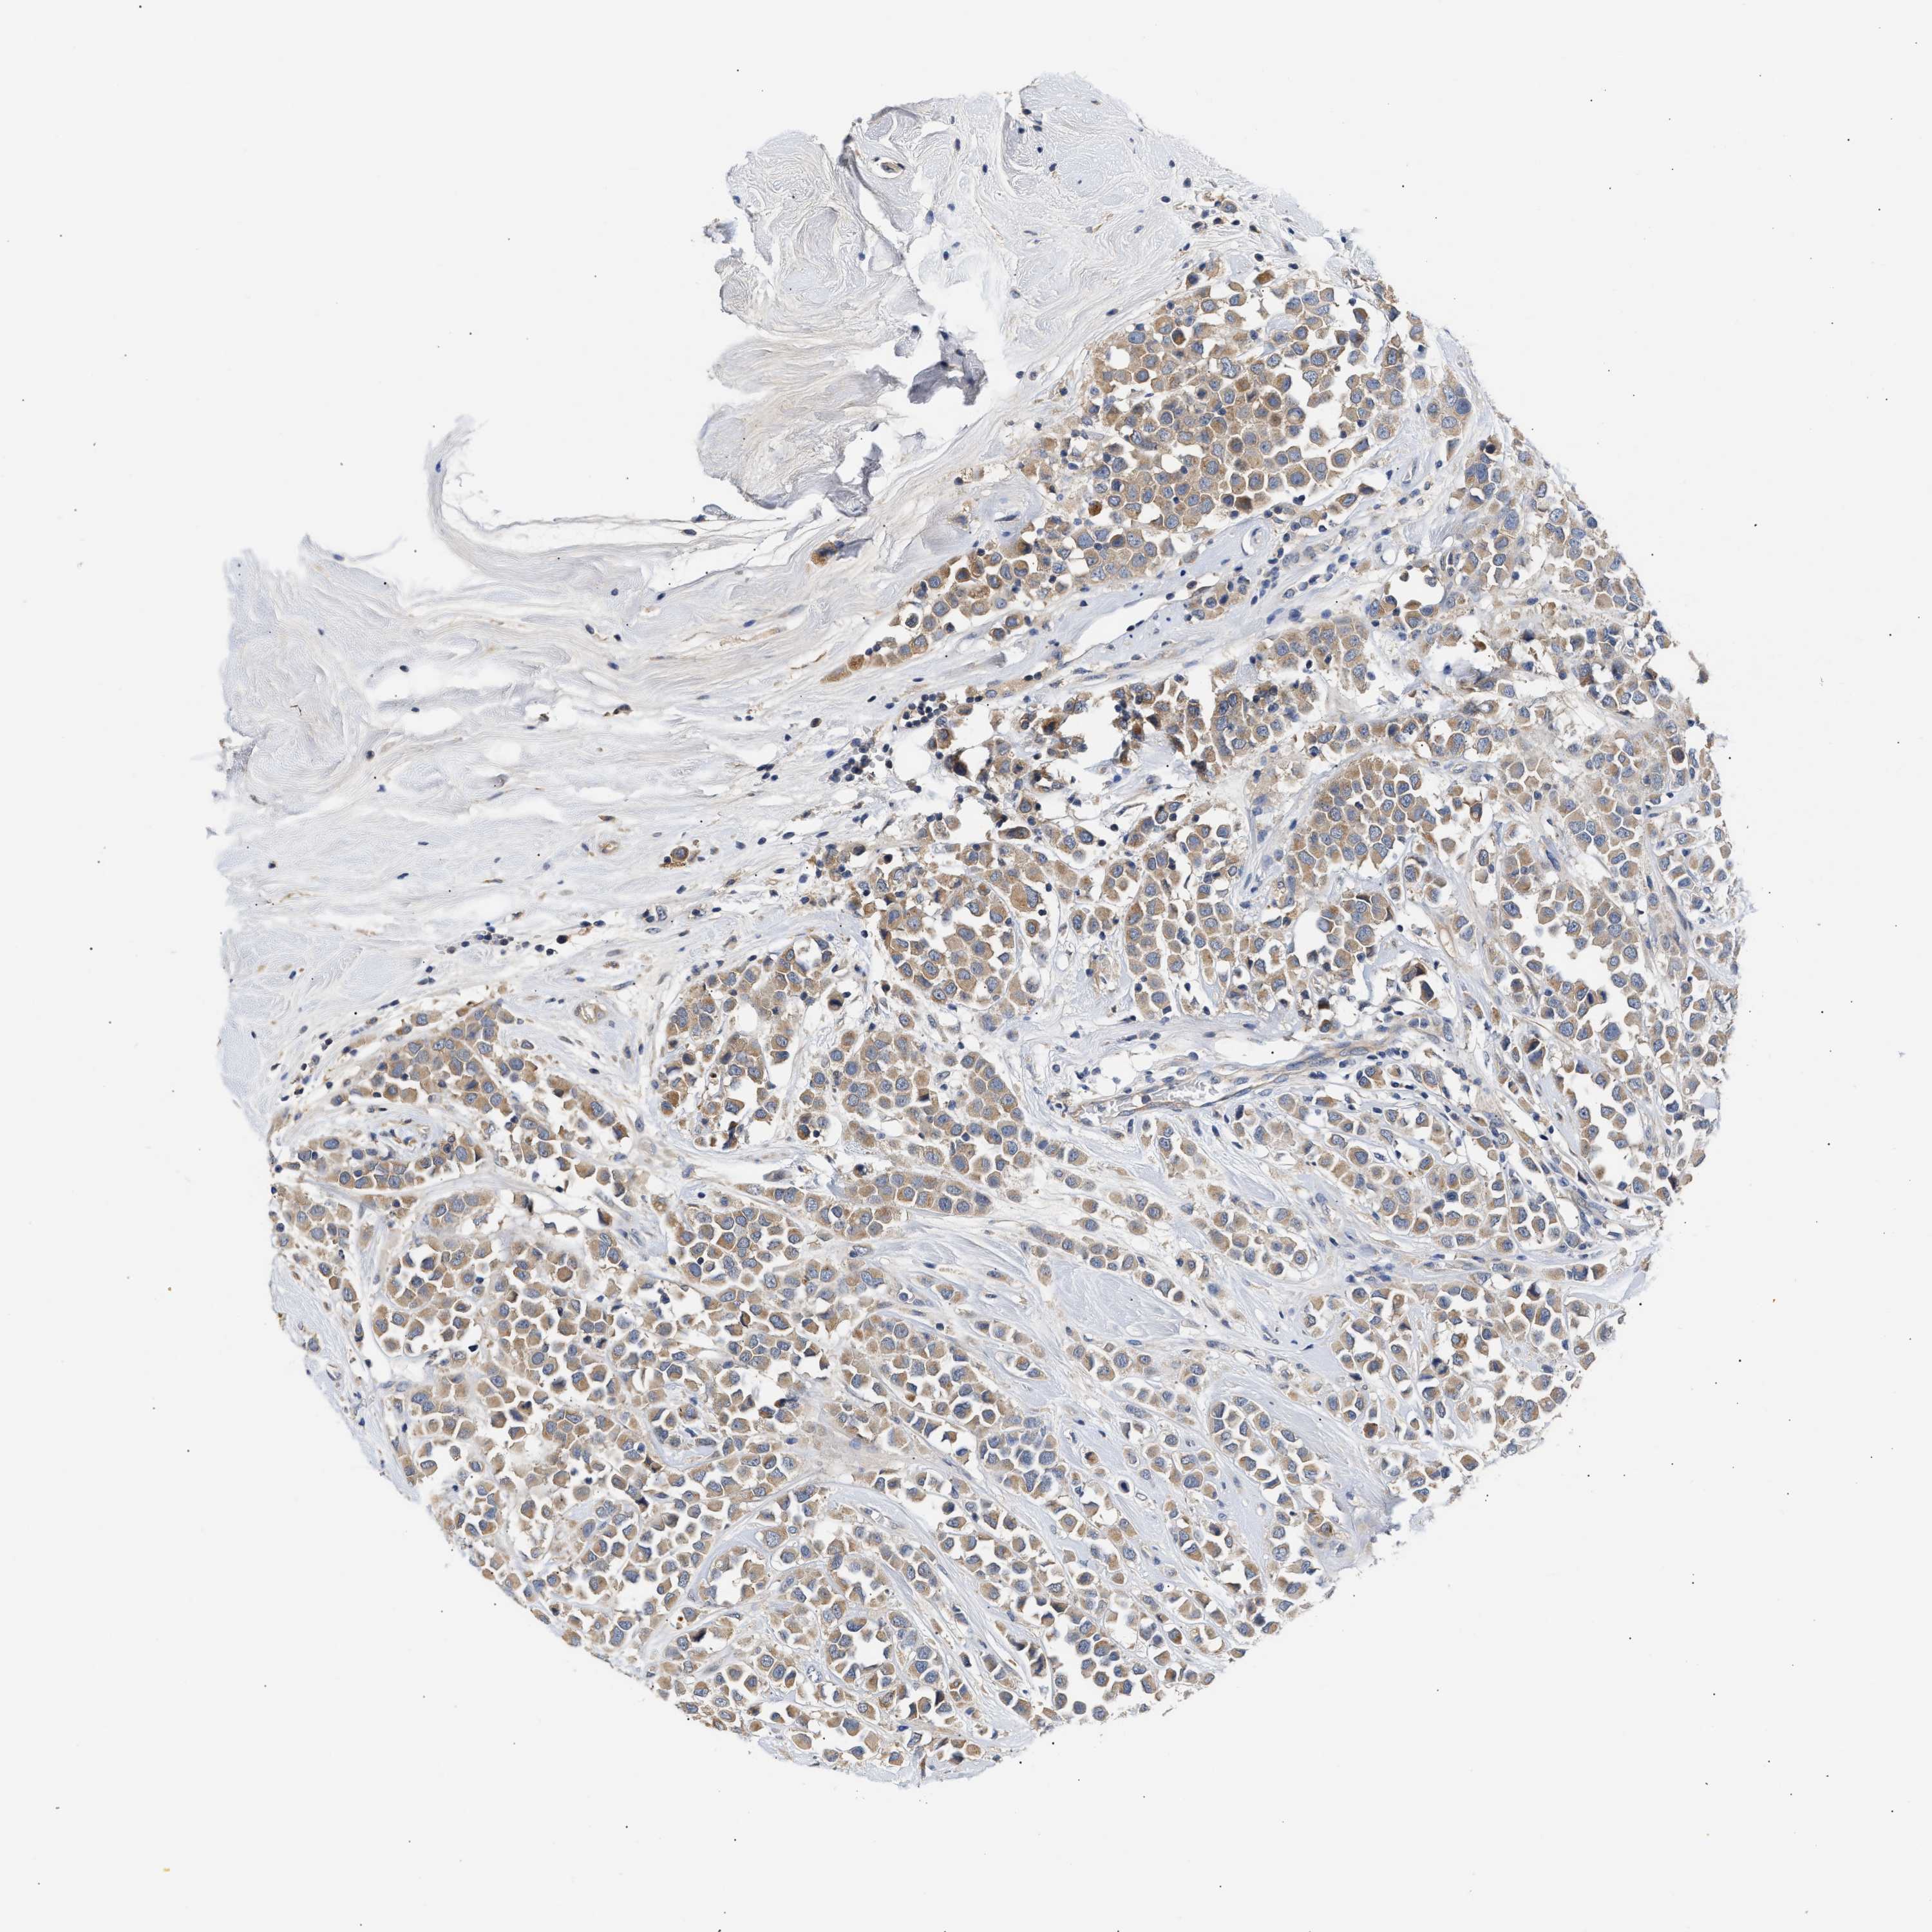

CANCER BREAST CANCER Show tissue menu

BRCA TCGA BRCA VALIDATION PROTEIN EXPRESSION